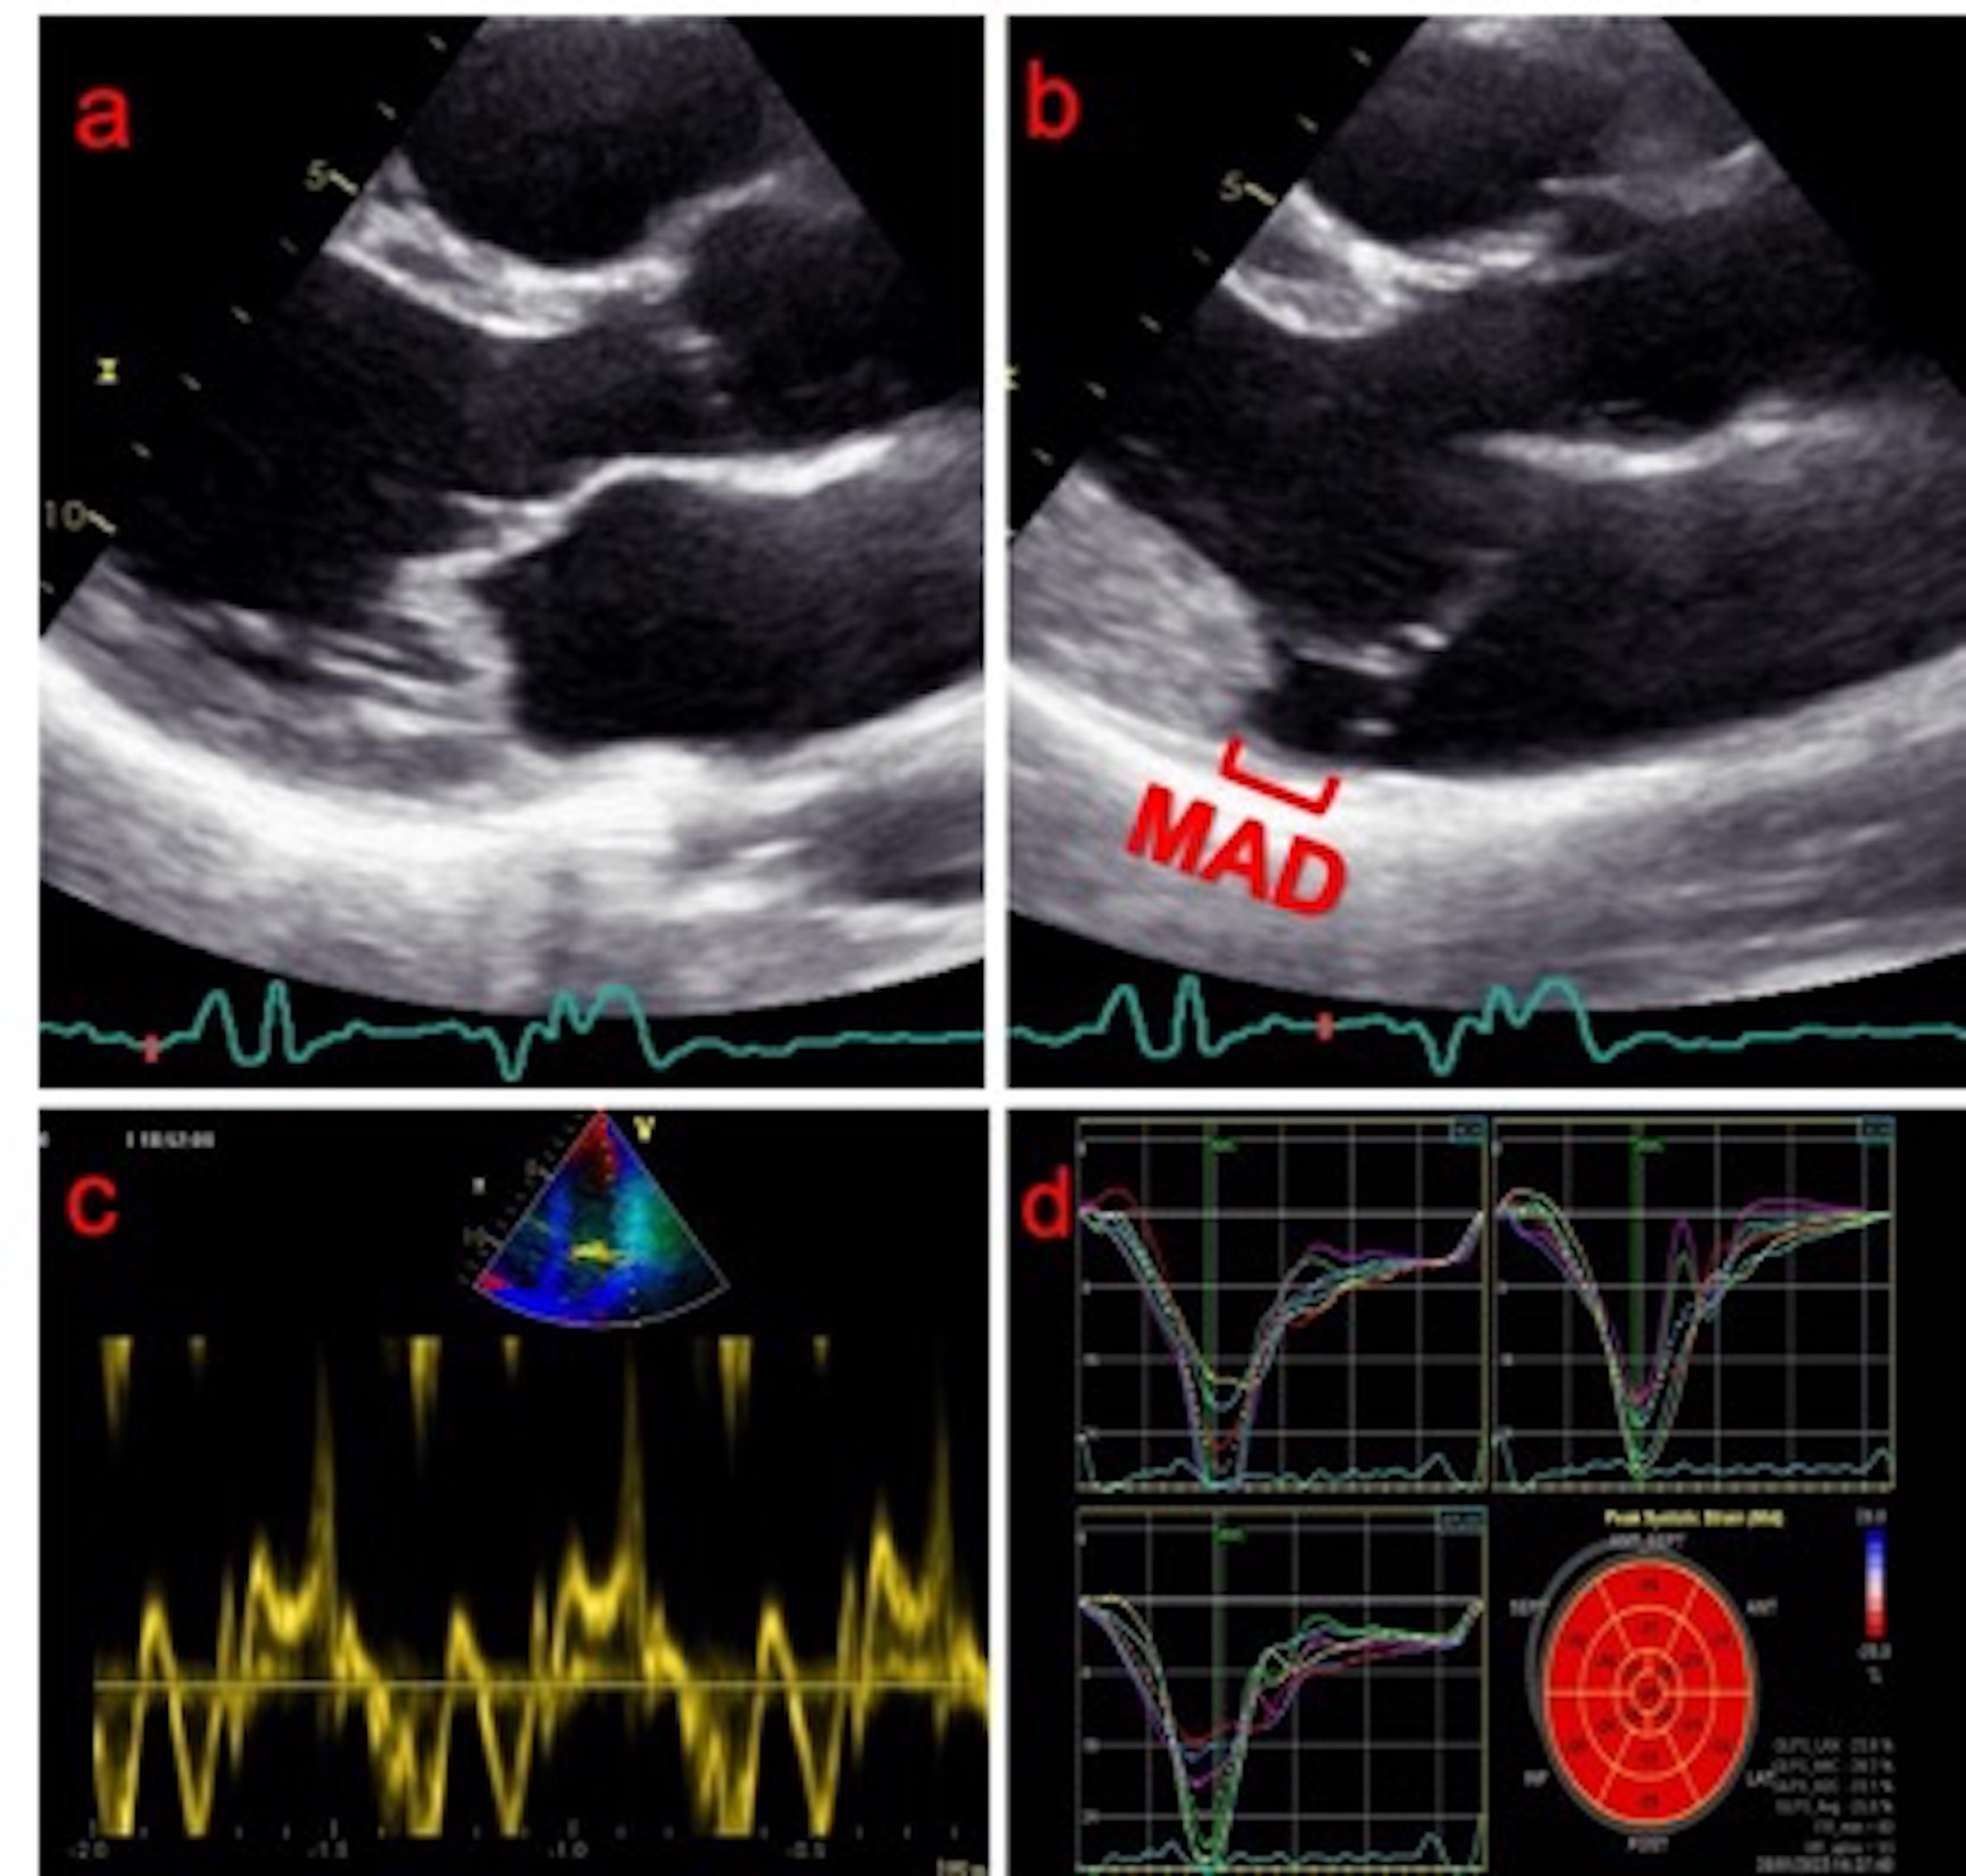

Fig. 1.Echocardiographic findings of mitral valve prolapse and

mitral annular disjunction. (a) Transthoracic parasternal long axis

echocardiographic view of a bileaflet mitral valve prolapse during end-diastole.

(b) Mitral annular disjunction is revealed during end-systole. (c) The

“Pickelhaube” sign (spiked systolic lateral mitral annular velocity

In pathological studies, MAD has been mainly related to MVP with floppy mitral

valve and myxomatous degeneration rather than FED [1, 13, 14]. MAD can be easily

detected by transthoracic echocardiography (TTE) [2], and measured in the

parasternal long axis view during end-systole (Fig. 1b). It mainly affects the